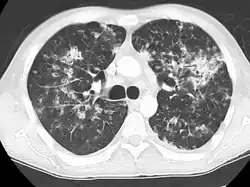

Miliary tuberculosis is a form of tuberculosis that is characterized by a wide dissemination into the human body and by the tiny size of the lesions (1–5 mm). Its name comes from a distinctive pattern seen on a chest radiograph of many tiny spots distributed throughout the lung fields with the appearance similar to millet seeds—thus the term "miliary" tuberculosis. Miliary TB may infect any number of organs, including the lungs, liver, and spleen.[2]

Tuberculosis of the lungs

Testing for miliary tuberculosis is conducted in a similar manner as for other forms of tuberculosis, although a number of tests must be conducted on a patient to confirm diagnosis.[3] Tests include chest x-ray, sputum culture, bronchoscopy, open lung biopsy, head CT/MRI, blood cultures, fundoscopy, and electrocardiography.[9] The tuberculosis (TB) blood test, also called an Interferon Gamma Release Assay or IGRA, is a way to diagnose latent TB. A variety of neurological complications have been noted in miliary tuberculosis patients—tuberculous meningitis and cerebral tuberculomas being the most frequent. However, a majority of patients improve following antituberculous treatment. Rarely lymphangitic spread of lung cancer could mimic miliary pattern of tuberculosis on regular chest X-ray. [14]

A case of miliary tuberculosis in an 82-year-old woman: